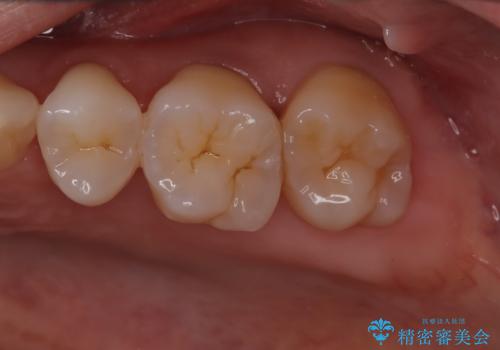

- 定期的にクリーニング(保険適応)に通って頂いている患者さんです。歯周ポケットが4ミリあったため歯茎を開いて歯石を除去するためにオープンフラップ術を行うことにしました。

歯周ポケットがそれほど深くない患者さんでしたが、いざ歯茎を開いてみるとそこにはたくさんの歯石がありました。もし歯周ポケットが4ミリだからと言って放置していれば数年後には、沢山の骨が無くなっていたことが予期出来ます。現段階で歯茎の下にある歯石を除去することにより骨が無くなることを予防する事が出来ました。